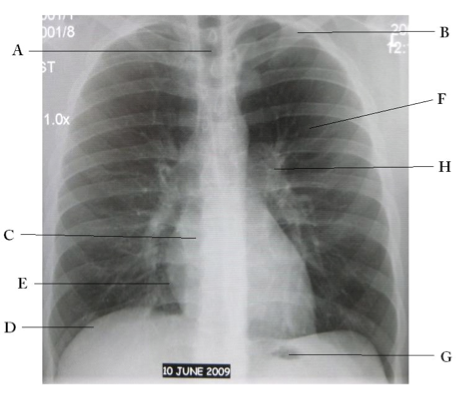

Name the structures according to letter

A – Trachea

B – Clavicle

C – Right Atrium

D – Diaphragm

E – Cardiophrenic angle (Costocardio)

F – Left upper lobe

G – Gastric Bubble

H – Left Hilum